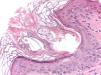

Pruebas complementariasSe llevó a cabo una biopsia en sacabocados de 2mm en la región preauricular izquierda. El estudio histológico demostró la presencia de 2 infundíbulos foliculares dilatados, con presencia de focos de hiperqueratosis compacta, asociados a la presencia de un ácaro en ambos (fig. 3). En la dermis subyacente se observaba un leve infiltrado inflamatorio linfocitario perivascular.